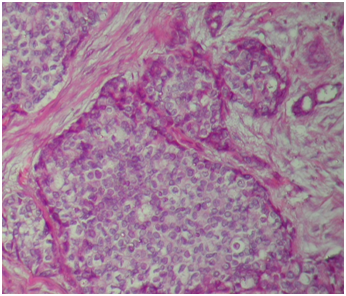

Ten percent neutral buffered formalin was used for fixation and 3 to 5 mm thick representative tissue biopsies were then processed in an automatic tissue processor using SLEE (mtp) processing machine. The blocks prepared by embedding the tissue in paraffin wax, then sectioned at 4μm using micro Tec laborgeräte microtome, and stained with hematoxylin and eosin (Figure 1) for light microscopy. Four sections (4μm in thickness) from each one of sixty biopsies were prepared for histochemical study after dewaxation as follows:

Figure 1 Section of Invasive ductal carcinoma (IDC), H&E X10.

The 60 breast lesions consist of 35/60 (58.3%) malignant tumors and 25/60 (41.7%) benign breast lesions (Table 2). For the 35 malignant samples Immunohistochemically stained for ER, there were 12/35 (34.3%) showed positive expression and 23/35 (65.7%) showed negative expression. From benign samples, there was 8/25 (32%) ER positive (Figure 3B) and 17/25 (68%) ER negative (Figure 3A). Out of the total study subjects, there was 20/60 (33.3%) ER positive as shown in Table 1&2. Regarding VanGieson, there were 53 positive stained samples (Figure 2A), of them 18/53 (34%) ER positive and 35/53 (66%) ER negative. For the 7 VanGieson, negatively stained samples were 2/7 (28.6%) ER positive and 5/7 (71.4%) ER negative. The correlation between collagen fibers and ER status was found to be statistically significant (P-value = 0.000). Masson trichrome resulted in 46 positive stained samples (Figure 2B), of them were 15/46 (32.6%) ER positive and 31/46 (67.4%) ER negative. For the 14 Masson, trichrome negative stained samples were 5/14 (35.7%) ER positive and 9/14 (64.3%) ER negative. The correlation between collagen fibers and ER status was found to be statistically significant (P-value = 0.000). Verhoeff method resulted in 38 positive stained samples (Figure 2C) distributed as 13/38 (34.2%) ER positive and 25/38 (65.8%) ER negative. For the 22 Verhoeff, negatively stained samples were 7/22 (32%) ER positive and 15/22 (68%) ER negative. The correlation between elastic fibers and ER status was found to be statistically significant (P value =0. 039). Silver stained samples exhibited 39 positive samples (Figure 2D) were 13/39 (33.3%) ER positive and 26/39 (66.7%) ER negative. For the remaining 21Silver stained negative samples were 7/21 (33.3%) ER positive and 14/21 (66.7%) ER negative.